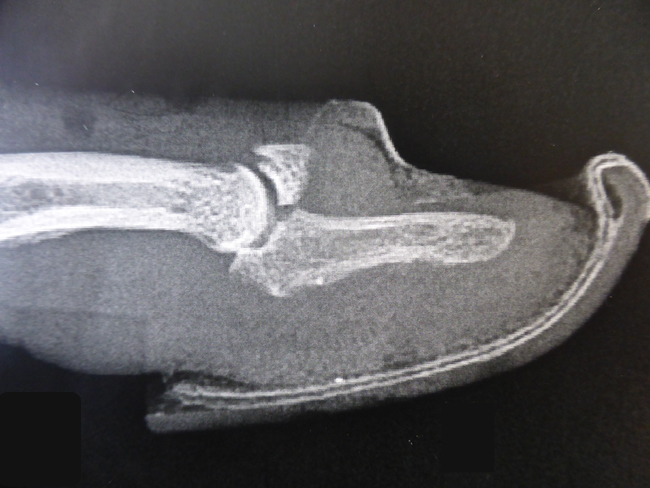

Toutefois lorsque le résultat n’est pas bon et qu’il persiste un déficit d’extension de l’articulation interphalangienne discale (IPD), la déformation peut s’étendre à l’ensemble du doigt: La traction du tendon extenseur se concentre sur la phalange intermédiaire et provoque une hyper extension interphalangienne proximale (IPP). Cette déformation en chaîne s’appelle une déformation “col de cygne”.

Déformation en col de cygne:

Le recul de l’appareil extenseur au niveau de la dernière phalange entraîne une hyper extension IPP et défaut d’extension IPD

La déformation s’accentue alors de façon progressive avec le temps